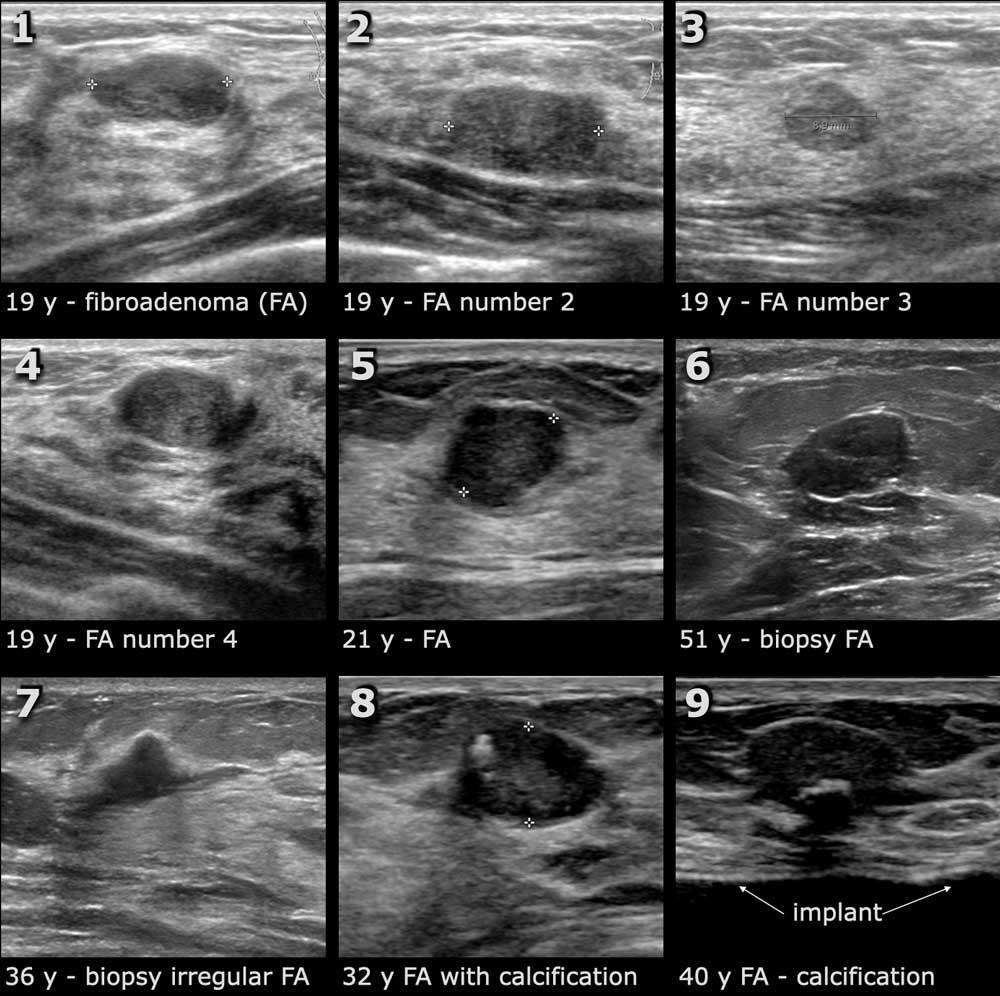

Dưới đây là một số ví dụ về u xơ tuyến vú.

Các tổn thương số 1-4 thuộc cùng một bệnh nhân.

Đây là một phát hiện thường gặp.

Khi phát hiện một u xơ tuyến vú, thường có thể tìm thấy thêm nhiều tổn thương khác.

Tổn thương số 6 được sinh thiết do tuổi của bệnh nhân và kết quả cho thấy là u xơ tuyến vú.

Tổn thương số 7 được sinh thiết vì có hình dạng không đều và hình ảnh gợi ý ung thư biểu mô.

Kết quả cũng cho thấy đây là u xơ tuyến vú.

U xơ tuyến vú đôi khi có vôi hóa, nhưng các vôi hóa này có kích thước lớn hơn so với các vôi hóa nhỏ thường gặp trong ung thư biểu mô.

Vi vôi hóa như thấy trong ung thư biểu mô ống tại chỗ (DCIS) – vốn có thể là tổn thương tiền ung thư – thường không quan sát được trên siêu âm.

Trong việc phát hiện DCIS, chụp nhũ ảnh (mammography) có nhiều ưu thế hơn.